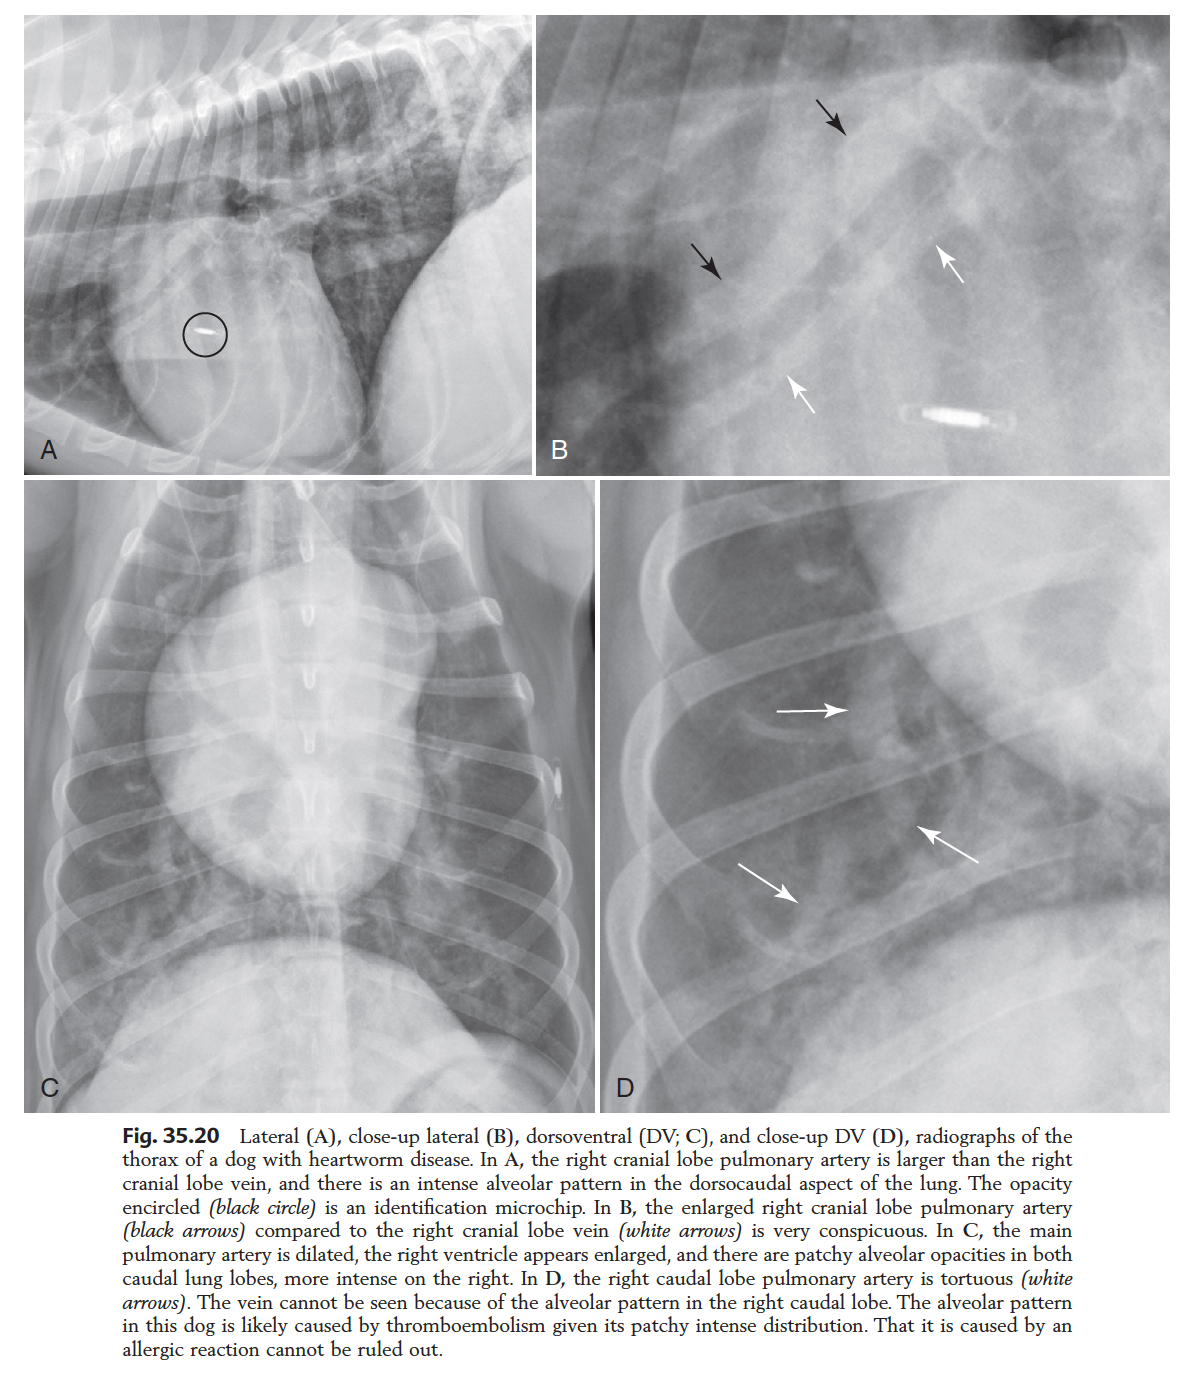

Pulmonary hypertension 2ry to HEARTWORM